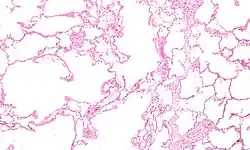

| Micrograph of an emphysematous lung; emphysema is a respiratory disease, strongly associated with smoking. H&E stain. | |

Asthma, chronic bronchitis, bronchiectasis and chronic obstructive pulmonary disease (COPD) are all obstructive lung diseases characterised by airway obstruction. This limits the amount of air that is able to enter alveoli because of constriction of the bronchial tree, due to inflammation. Obstructive lung diseases are often identified because of symptoms and diagnosed with pulmonary function tests such as spirometry. Many obstructive lung diseases are managed by avoiding triggers (such as dust mites or smoking), with symptom control such as bronchodilators, and with suppression of inflammation (such as through corticosteroids) in severe cases. One common cause of COPD including emphysema, and chronic bronchitis, is tobacco smoking, and common causes of bronchiectasis include severe infections and cystic fibrosis. The definitive cause of asthma is not yet known.[4]